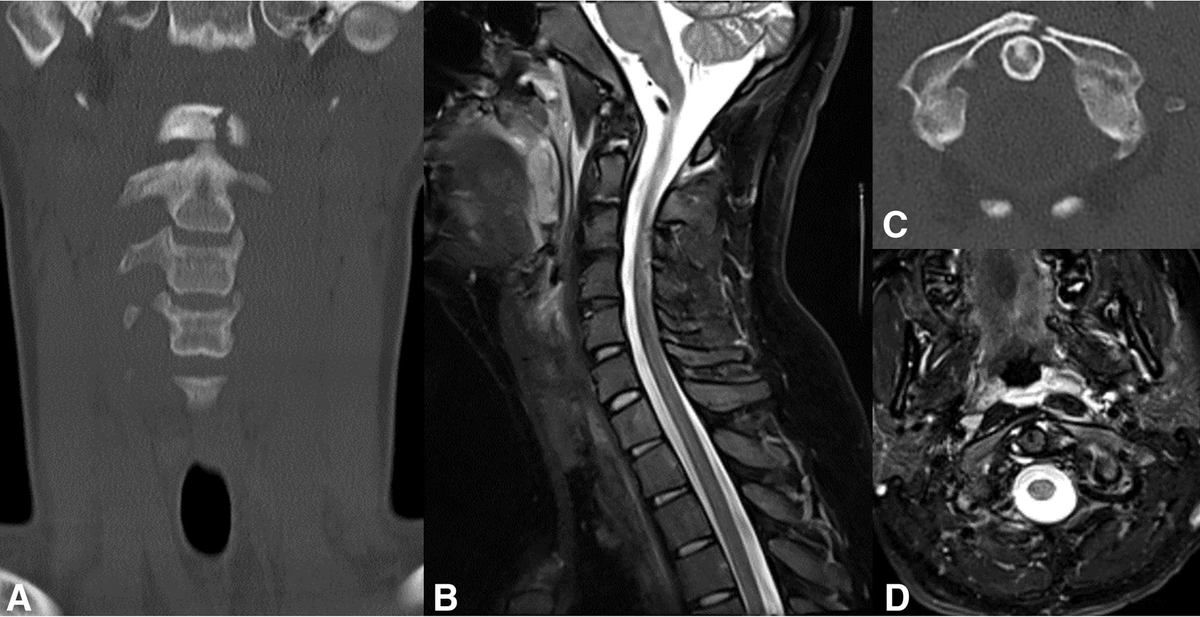

From the April-June 2023 Issue of #Neurographics: Imaging of Blunt Cervical Spine Ligamentous Injuries: Bridging the Gap between Neuroradiologists and Neurosurgeons ow.ly/ubHS50Pfk4K